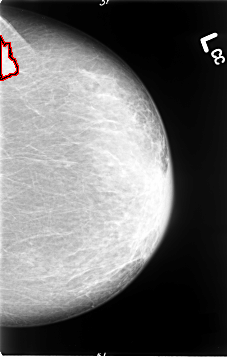

B_3064_1.LEFT_MLO

LEFT_MLO LINES 4640 PIXELS_PER_LINE 2912 BITS_PER_PIXEL 12 RESOLUTION 50 OVERLAY

FILE: B_3064_1.LEFT_MLO.OVERLAY

TOTAL_ABNORMALITIES 1

ABNORMALITY 1

LESION_TYPE MASS SHAPE IRREGULAR MARGINS SPICULATED

ASSESSMENT 5

SUBTLETY 5

PATHOLOGY MALIGNANT

TOTAL_OUTLINES 1

BOUNDARY